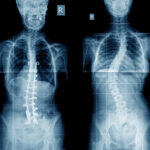

【側弯症でお悩みの方へ】ピラティススタジオnの代表が側弯症について解説

こんにちは。ピラティススタジオnの西口です。 当店でもこれまで側弯症でお悩みの方の整体やピラティスを行ってきました。 その中には、側弯症と診断を受けたことのある方もいれば、こちらが姿勢評価をして軽い側弯があると分かった方 […]